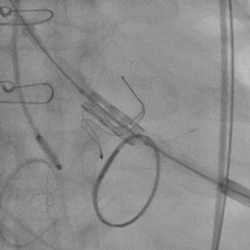

黄焕雷主任带领具有丰富经验的心脏麻醉医师、体外循环师、超声心动图医师、手术室、心外重症监护室、心脏导管室多学科团队,联合心内科专家谢年谨主任,为蔡先生实施小切口下、介入途径的主动脉瓣“瓣中瓣”、二尖瓣“环中瓣”的同期植入手术:黄主任首先在患者左前胸做一小切口,暴露患者的心尖,在跳动的心脏上“绣”上荷包作为介入导管、瓣膜的植入“门户”;随后,黄焕雷主任在超声心动图、放射透视的引导下,将一钢针在患者心尖“扎”入患者心脏内,为之后的瓣膜植入作为引导,具体来说就是将预先选择适合患者大小的生物瓣膜折叠、压缩入细长的输送管道内,好比将瓣膜这一“弹头”安放在输送导管这颗精准制导的“火箭”上,而黄主任的双手则控制这一精准发射和制导,再将瓣膜输送到主动脉合适的位置后释放,新的主动脉瓣便牢固地“卡”在了原有的主动脉瓣架内。经过透视和超声心动图评估,主动脉瓣位置合适,开放、闭合功能良好。随后,黄主任通过这一根钢针和输送导管,利用类似的方式,调整“火箭”的发射轨道,在原有二尖瓣人工瓣环内植入预先选择好大小的二尖瓣生物瓣膜,经过影像学方式评估,新植入的二尖瓣生物瓣工作良好。

术后主动脉根部造影

术后左室造影